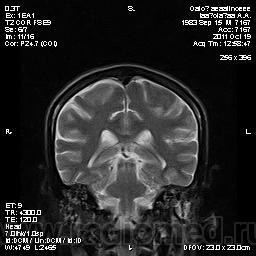

Молодой человек, жалуется только на головные боли и слабость в правой руке и ноге (около месяца).

Пациент полуасоциальный, нельзя исключить анамнез наркоманский....

ППН (включая ячейки пирамидок и сосцевидные отростки) тотально заполнены жидкостным компонентом...

Колеги, спасибо за высказывания. В данном случае про наркоманский анамнез указано не спроста... Есть мнение, что в этом лежит точка отсчета.... По поводу абсцесса и гематомы - не согласен; по поводу первого - нет соответствющей клиники, по поводу второго - не характерна локализация и сигнальные характеристики. Не буду томить общественность касательно собственного мнения. Есть две гипотезы, о которых думается в данном случае: прогрессирующая лейкоэнцефалопатия и новообразование... Но без контраста их не разрешить...